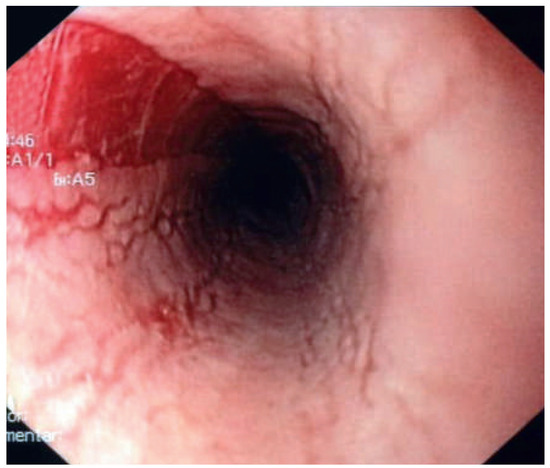

A 41-year-old women with Ebstein’s anomaly required tricuspid valve replacement six years ago. At that time a biological prosthesis was implanted. The tricuspid valve prosthesis became severely stenotic within five years. Instead of re-do surgery, th...